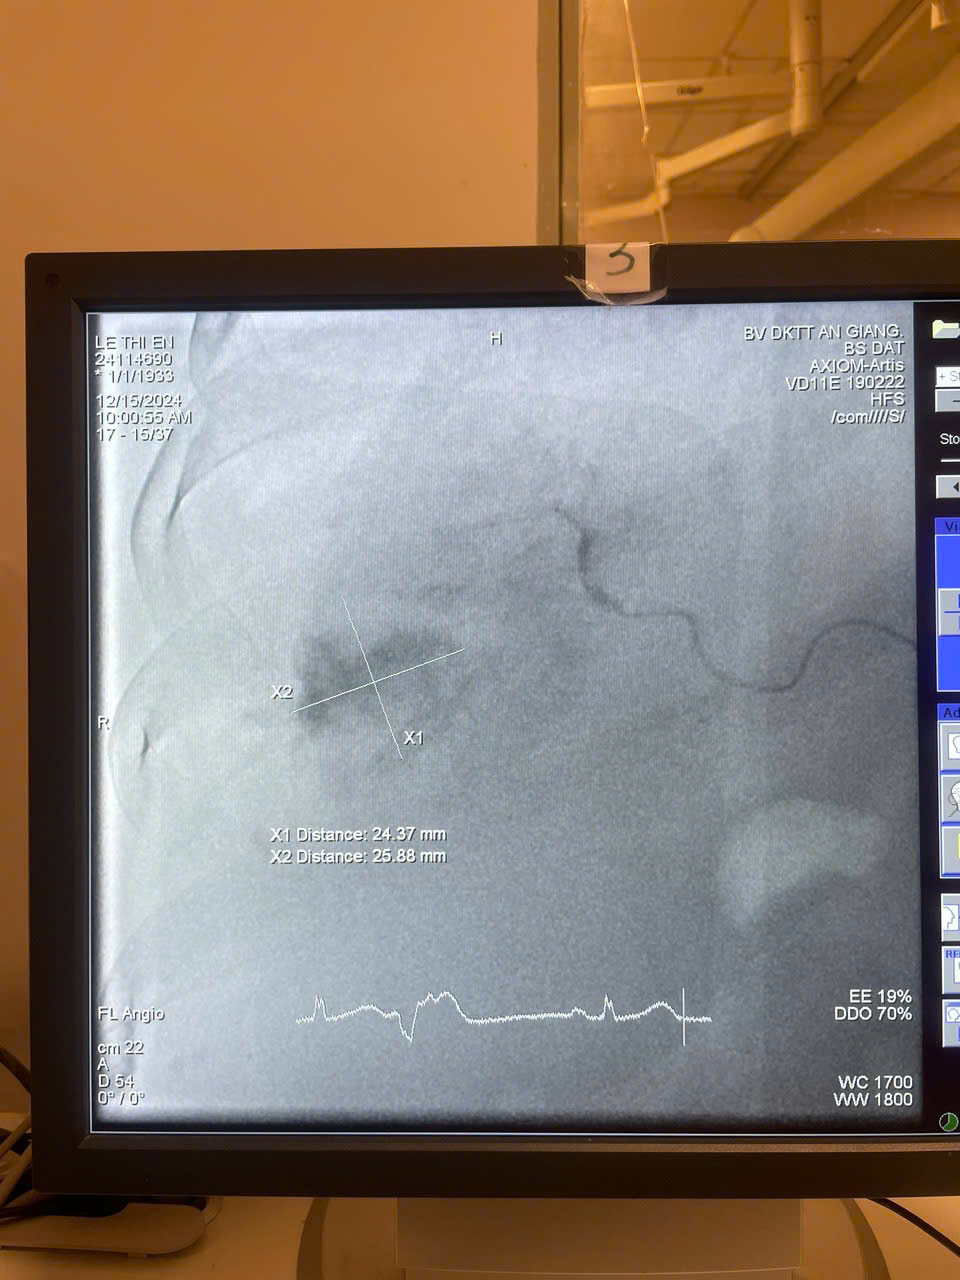

Từ ngày 15/12/2024 đến nay, Bệnh viện Đa An Giang đã thực hiện thành công nhiều ca can thiệp TACE (nút mạch hóa chất chọn lọc qua động mạch gan) để điều trị ung thư tế bào gan nguyên phát giai đoạn trung gian. Kỹ thuật được triển khai dưới sự hỗ trợ chuyên môn của Bệnh viện Đa khoa Trung ương Cần Thơ theo Đề án 1816.

Các bệnh nhân, lớn tuổi nhất 91 tuổi và nhỏ nhất 60 tuổi, đã được tiếp nhận, chẩn đoán, điều trị và chăm sóc toàn diện tại Khoa Ung bướu, với sự phối hợp chặt chẽ cùng ê-kíp can thiệp Khoa Chẩn đoán hình ảnh, do BS.CKII. Lê Tấn Đạt – Phó trưởng khoa Chẩn đoán hình ảnh trực tiếp thực hiện.